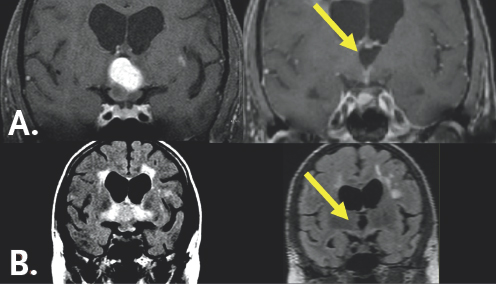

Six months later, Anne’s condition had grown considerably worse. She had begun to suffer from headaches. Her issues with eyesight had continued to worsen. Her short-term memory loss was now severe. Around this time, Anne’s ophthalmologist sent her to a second doctor specializing in neuro-ophthalmology. The neuro-ophthalmologist was very troubled to hear of Anne’s symptoms and ordered magnetic resonance imaging (MRI) of her brain. The MRI revealed a large tumor filling the third ventricle—a cavity immediately behind the optic chiasm and resting in between the hypothalamic centers (Figure 9.1). The tumor was associated with extensive inflammation that was almost certainly the cause of Anne’s visual symptoms and memory loss.

(Left) A white blob is highlighted by a yellow arrow in the center of the figure. It is surrounded by gray colored variations contained within a black and dark gray boarder. (Right) A white colored region resembling an 'X' surrounds a black butterfly-looking structure. The bottom right portion is highlighted by a yellow arrow. It is surrounded by light gray coloration which is contained within a black and white boarder.

FIGURE 9.1 Pre-operative MRI. MRI (A) demonstrates a chordoid glioma (yellow arrow) occupying the confines of the third ventricle that appears bright after being injected with contrast. The underlying optic nerves and chiasm are swollen and infamed. MRI (B) shows extensive tissue damage associated with the mass (yellow arrow) that appears as a bright signal.